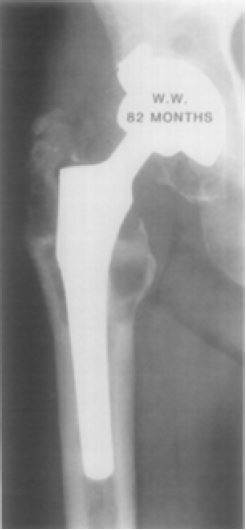

La evolución de los hallazgos de todos los cirujanos ortopedistas se consolidaron en los años sesenta, cuando el Dr. Charnley introdujo tres conceptos clave que revolucionaron los remplazos articulares y mejoraron exponencialmente la supervivencia de los pacientes, que se reportó entre el 77 % y el 81 % pasados 25 años de la intervención ( figura 2); por esto, los remplazos articulares de la cadera pasaron a llamarse la cirugía del siglo( 17, 18, 19). Las contribuciones del Dr. Charnley incluyeron la artroplastia de baja fricción, que se logra asegurando que el componente de la cabeza femoral sea del menor radio posible respecto al componente acetabular, de manera que produce una fuerza de torque más baja en la copa del acetábulo. Además, el Dr. Charnley popularizó el uso de cemento óseo de polimetilmetacrilato (PMMA) para la fijación de la prótesis a la superficie ósea subyacente y, por último, el uso de polietileno de alta densidad para la copa acetabular ( 17, 20).

Sin embargo, llamaba la atención el aflojamiento temprano del vástago cementado. En 1970, investigadores encontraron que el cemento óseo generaba una reacción de fagocitosis al PMMA y posterior osteólisis, por lo que terminaba en aflojamiento aséptico de las prótesis ( 21, 22, 23). El estudio subsecuente del aflojamiento de las prótesis permitió aclarar que este no se atribuía a la fagocitosis del PMMA, sino que se trataba de la fagocitosis del polietileno, que generaba osteólisis, migración en la interfase periprotésica de los detritos particulados y terminaba en el aflojamiento subsecuente de los componentes. De ahí data el inicio de investigaciones en tecnología de alta calidad del polietileno, que disminuyen el desgaste y el aflojamiento ( 24, 25, 26) ( figura 3).

De forma simultánea, inició el desarrollo de los remplazos articulares no cementados, que se utilizan actualmente y cuya tecnología en materiales, recubrimiento, características de las prótesis, así como los diferentes abordajes quirúrgicos y su estandarización, comprende toda una evolución por medio de la ingeniería biomédica y la cirugía ortopédica ( 17).